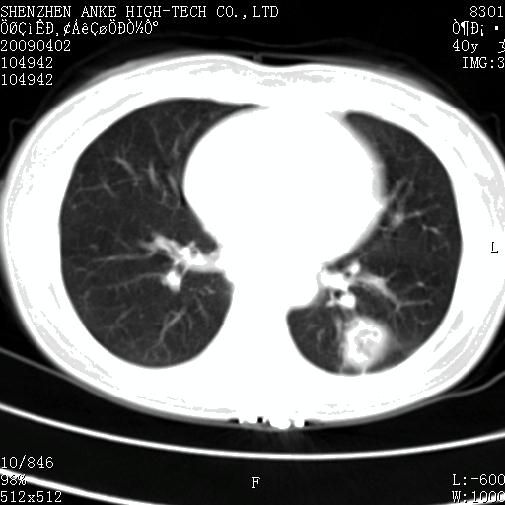

以下是引用随光逐影在2009-4-2 12:16:00的发言:[br]考虑左肺下叶背段继发性肺结核,结核球形成;建议追踪复查。

以下是引用gudu医生在2009-4-2 11:27:00的发言:[br]周围型肺癌

以下是引用卜一在2009-4-2 13:31:00的发言:[br][br] [br] 空洞壁厚不均 胸膜凹陷征。周围型肺癌可能 不排除干酪坏死型肺结核及坏死性肉芽肿。 [br] [br]支持!

以下是引用ct诊断高手在2009-4-2 13:04:00的发言:[br]空洞壁厚不均 胸膜凹陷征。周围型肺癌可能 不排除干酪坏死型肺结核及坏死性肉芽肿。